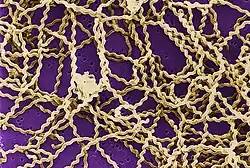

| Leptospira magnified 200-fold with a dark-field microscope. | |

Leptospirosis is caused by spirochaete bacteria that belong to the genus Leptospira, which are aerobic,[8] right-handed helical,[12] and 6–20 micrometers long.[7] Like Gram-negative bacteria, Leptospira have an outer membrane studded with lipopolysaccharide (LPS) on the surface, an inner membrane and a layer of peptidoglycan cell wall. However, unlike Gram-negative bacteria, the peptidoglycan layer in Leptospira lies closer to the inner than the outer membrane. This results in a fluid outer membrane loosely associated with the cell wall.[25] In addition, Leptospira have a flagellum located in the periplasm, associated with corkscrew style movement.[7] Chemoreceptors at the poles of the bacteria sense various substrates and change the direction of its movement.[12] The bacteria are traditionally visualised using dark-field microscopy without staining.[7]

A total of 66 species of Leptospira has been identified. Based on their genomic sequence, they are divided into two clades and four subclades: P1, P2, S1, and S2.[26] The 19 members of the P1 subclade include the 8 species that can cause severe disease in humans: L. alexanderi, L. borgpetersenii, L. interrogans, L. kirschneri, L. mayottensis, L. noguchii, L. santarosai, and L. weilii.[12][26] The P2 clade comprises 21 species that may cause mild disease in humans. The remaining 26 species comprise the S1 and S2 subclades, which include "saprophytes" known to consume decaying matter (saprotrophic nutrition).[26] Pathogenic Leptospira do not multiply in the environment. Leptospira require high humidity for survival but can remain alive in environments such as stagnant water or contaminated soil. The bacterium can be killed by temperatures of 50 °C (122 °F) and can be inactivated by 70% ethanol, 1% sodium hypochlorite, formaldehyde, detergents and acids.[27]

Leptospira are also classified based on their serovar. The diverse sugar composition of the lipopolysaccharide on the surface of the bacteria is responsible for the antigenic difference between serovars.[12] About 300 pathogenic serovars of Leptospira are recognised. Antigenically related serovars (belonging to the same serogroup) may belong to different species because of horizontal gene transfer of LPS biosynthetic genes between different species. Currently, the cross agglutination absorption test and DNA-DNA hybridisation are used to classify Leptospira species, but are time-consuming. Therefore, total genomic sequencing could potentially replace these two methods as the new gold standard of classifying Leptospira species.[12]